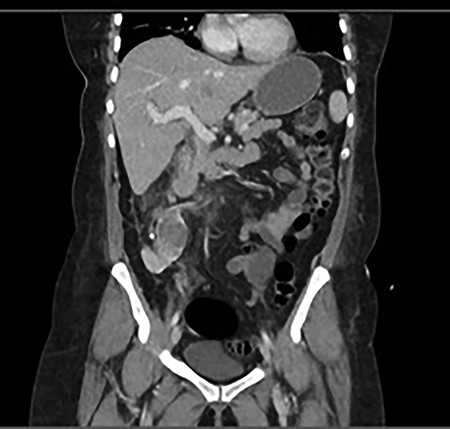

She was treated with ampicillin and a reduced dose of gentamicin given her AKI. Because of persisting shock, this patient was admitted to the intensive care unit (ICU) for inotropic support. Subsequently, both the urine and blood culture grew Escherichia coli. A repeat CT with contrast was performed due to persisting high fevers and severe right lower quadrant pain, which showed an early renal abscess (Fig. 2). Because of ongoing sepsis and absence of urology service in our hospital, the patient was transferred to another hospital where a urology service was available. She subsequently had insertion of a ureteric stent. The patient continued to improve post stent insertion and discharged when clinically well. She had removal of stone and ureteric stent 6 weeks later.

Progress CT showed worsening of perinephric inflammatory stranding and low-density area at the interpolar and upper pole of the right kidney representing an early renal abscess.